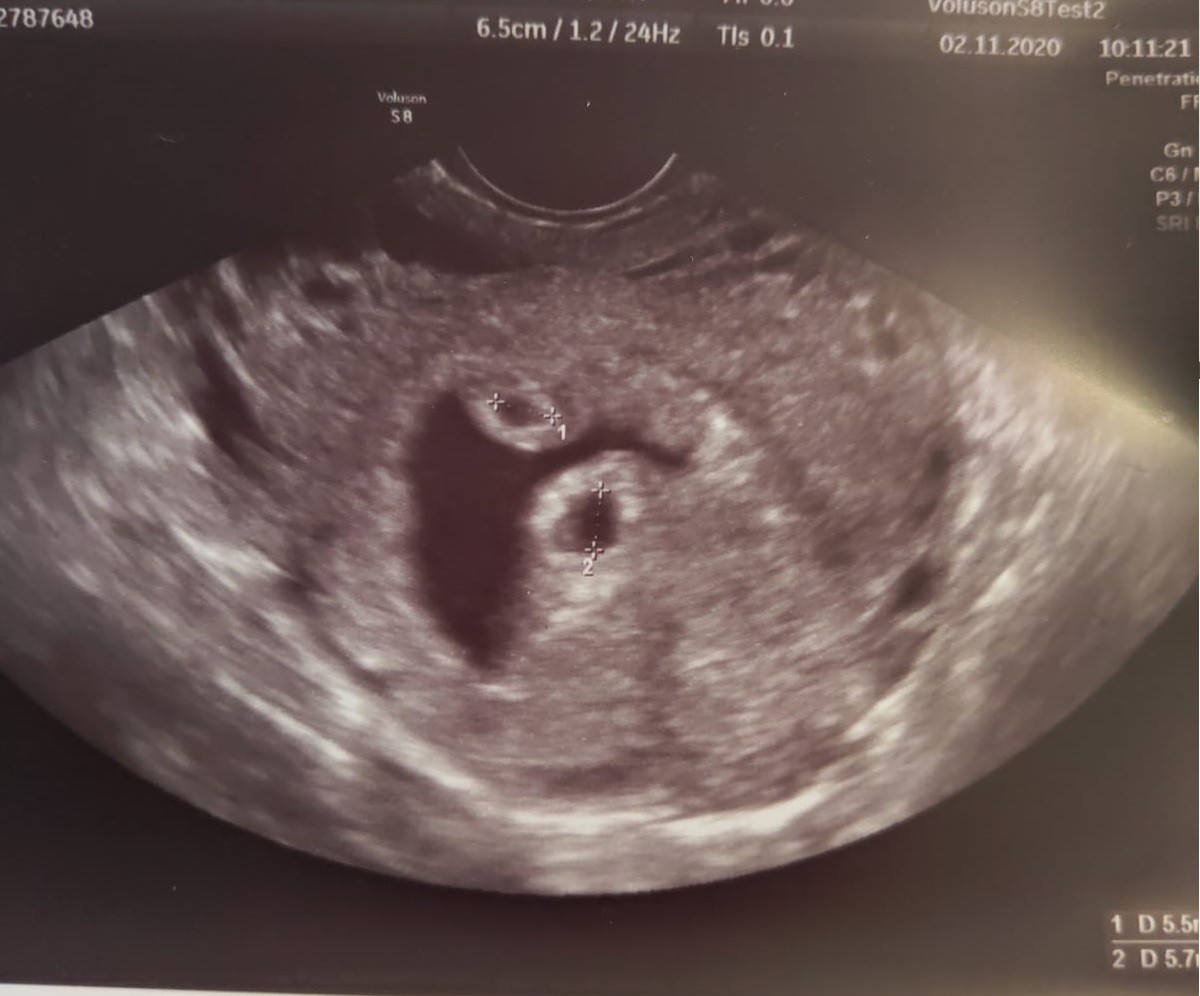

Hej dziewczyny. Ja wczoraj miałam USG pierwsze i oczywiście dzieciaki mniejsze niż powinny bo wczoraj powinny być 5 tydz 5 dzień a były jak 5 tydz i 2 dzień, ale moje zawsze tak mają i wiem, że jeszcze większa różnica się zrobi z czasem. Chyba nigdzie im się nie spieszy. Najważniejsze, że są dwa zarodeczki ❤ ❤

Więc tak jak chciałam będą bliźniaki :D